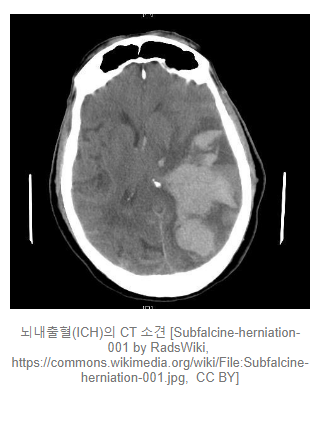

뇌내출혈 (Intracerebral hemorrhage)

연뇌막 안에 있는 뇌 실질에 출혈이 발생. CT에서 주로 둥글둥글하게 보입니다.

뇌내출혈은 외상에 의해서도 흔히 발생하며 고혈압, 당뇨, 음주, 폐경 등이 위험요소입니다. 즉, 해당 질병들이 있을 경우에 자발적으로 뇌내출혈이 발생할 확률이 올라갑니다.

증상은 두통과 함께 출혈이 발생한 부위의 뇌 기능에 따라 상이하게 나타납니다.

양이 적을 경우에는 입원하여 혈압조절 및 대증적 치료를 통해 출혈 자체는 치료가 되지만, 후유증이 주로 남기 때문에 장기적인 재활치료가 필요할 수 있습니다. 양이 많을 경우에는 수술이 필요합니다.